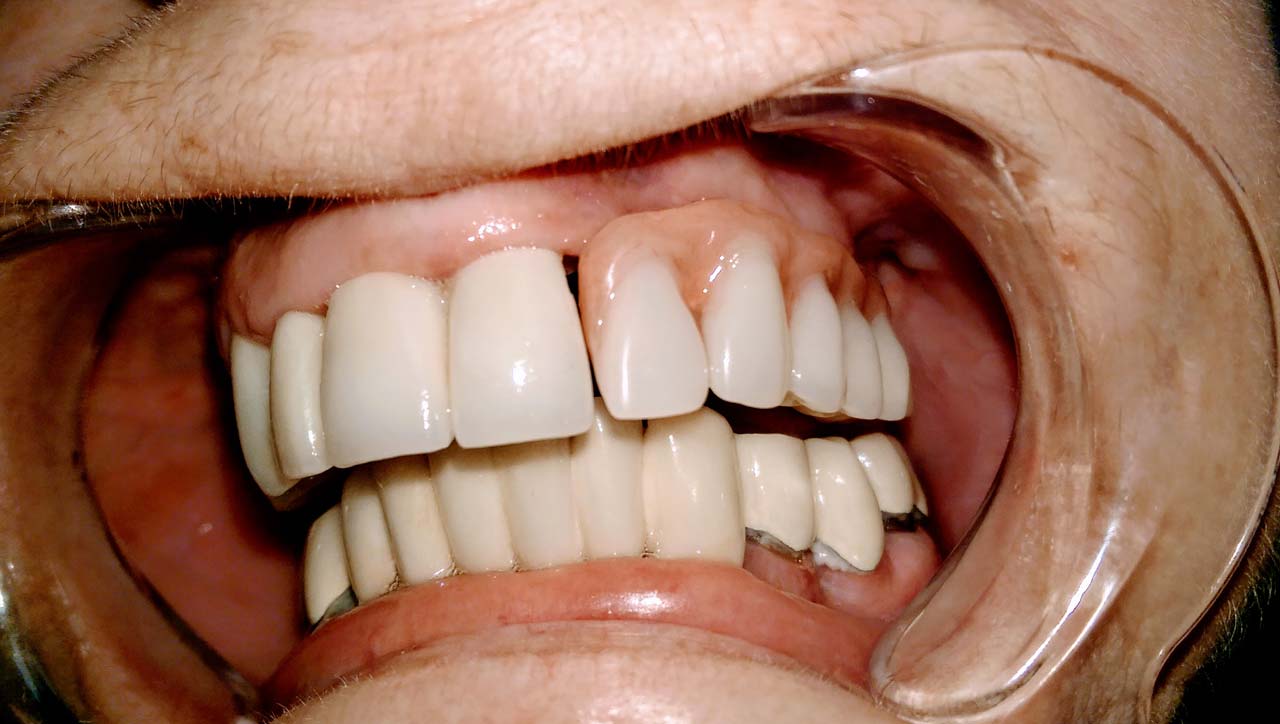

Ismét egy teljes szájüregi rehabilitáció két lépésben. Először az alsó fogak lettek kihúzva és azonnal implantálva, híddal ellátva, majd később a felső. IHDE svájci azonnal terhelhető implantátumok és cirkónium hidak. Dr. Kelemen Péter és a Symbion Fogtechnika közös munkája.